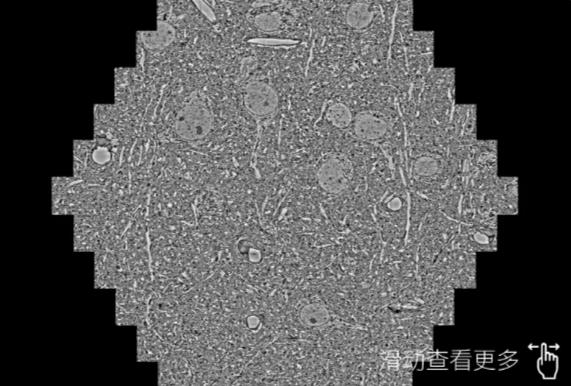

鼠脑切片。左图使用闵行蔡司闵行扫描电镜MultiSEM706对165μmx143pm面积区域成像,耗时仅需1.5秒。右图为鼠脑切片中30μm区域放大效果。样品由芝加哥大学B.Kasthuri提供。

使用蔡司高速闵行扫描电镜MultiSEM对1mm²人脑皮层组织进行高分辨成像,并对其中的各种细胞结构进行三维重构分析。左图展示了2x3mm²组织平面中锥体神经元的三维重构效果。右图显示了局部体积神经元三维重构。图像由哈佛大学chtman实验室提供,渲染图由D. Berger 制作。